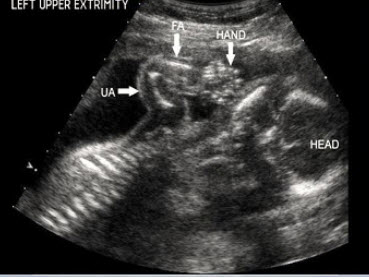

9、单项选择题

患者,男性,甲状腺一侧可触及包块,超声见边界清晰的低回声光团,包膜完整。如图所示,最可能的诊断为()